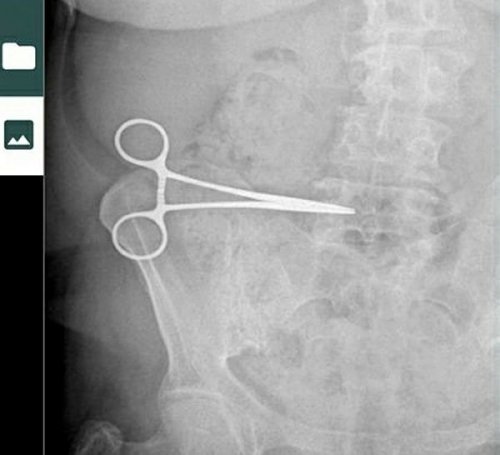

Kuşadası Gözde Hastanesi'nde estetik ameliyatı olan 61 yaşındaki Nurcihan Öğmen'in operasyon sırasında karnında unutulan makas, iki ay sonra çekilen röntgenle ortaya çıktı.

Aydın Devlet Hastanesi'nde çekilen röntgende sağ karın bölgesinde estetik operasyonu sırasında makas unutulduğunun ortaya çıktığını anlatan Nurcihan Öğmen, "Günlerce ağrı çektim. İnsan en azından bir bakmaz mı? İki ay beni muayene dahi etmedi. Doktor Levent Ateş'ten şikayetçiyim" dedi.

AVUKAT Mehmet Korkut, "Müvekkilim her hafta ameliyatın yapıldığı özel hastanedeki doktor Levent Ateş'e kontrol için gitmiş, dayanılmaz ağrılarının olduğunu belirtmiş ancak şüpheli umursamaz tavırlarla 'Geçer' denilerek müvekkilimi geri göndermiştir. Sonrasında Nurcihan Hanım'ın karnında klemp-makas unutulduğu ortaya çıkmıştır. Halbuki en temel tıbbi kurallara göre ameliyata başlamadan kullanılacak aletler sayılarak masaya konur ve ameliyat sonunda da sayılarak olası vücutta alet unutma riski minimuma indirilebilirdi" dedi.